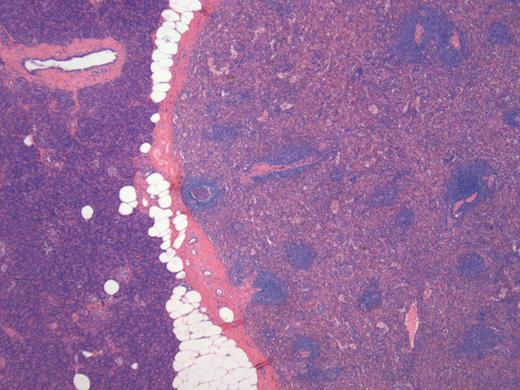

A 76-year-old male presented to his general practitioner with nausea, weight loss and change in bowel habit. A recent colonoscopy was unremarkable, a computed tomography (CT) abdomen and pelvis showed a homogenously enhancing 13-mm lesion in the tail of the pancreas, with the reported differentials including neuroendocrine tumour or a pancreatic adenocarcinoma. A subsequent magnetic resonance imaging (MRI) illustrated the lesion enhancing homogenously in the portal venous post-contrast phase suggesting a solid neoplastic lesion, likely to be primary (Fig. 1). He went on to have a distal pancreatectomy and splenectomy with an uneventful recovery. Pathology revealed a splenunculus with no evidence of malignancy (Fig. 2).

MRI: small round lesion in the pancreatic tail measuring 1×1 cm, enhancing homogenously in the portal venous post-contrast phase suggesting a solid neoplastic lesion. The differential includes primary pancreatic lesion such as a small mucinous cystic pancreatic tumour or an islet cell tumour